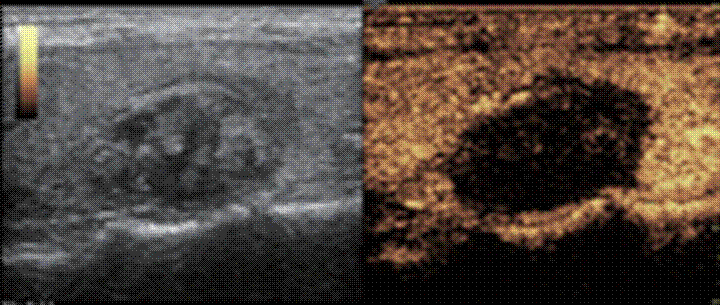

甲状腺实性结节超声造影为明显高增强 大小约4.4cmx2.6cmx2.7cm

消融治疗后超声造影患者甲状腺结节完全无增强,呈坏死改变